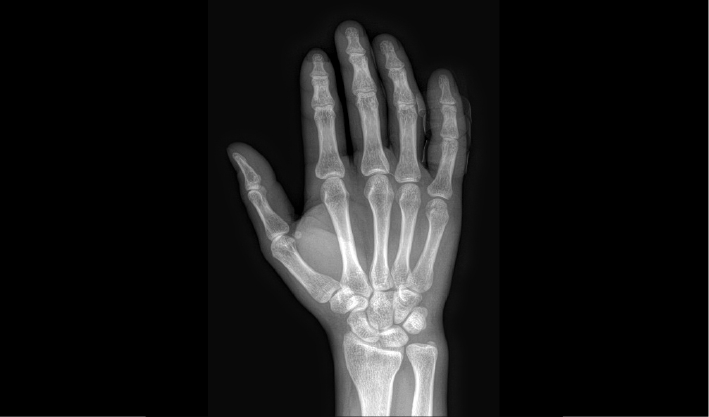

高清成像助力精准诊断

常规DR摄影检查,如:胸片位,腹部位,四肢位等。

成熟优秀的动态成像技术,在透视下实时观察内部器官运动状态,并可快速高清点片,动静结合,多视角精准观察病灶。